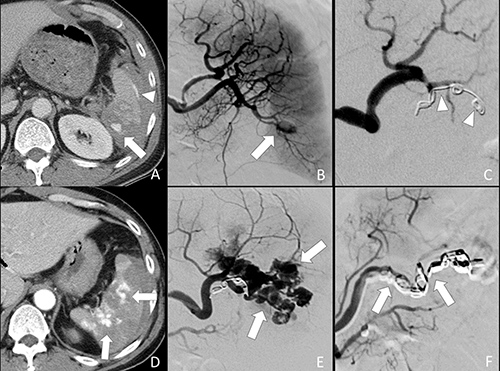

Technical success was achieved in all patients, defined by cessation of contrast medium extravasation or obliteration of pseudoaneurysm on post-embolization angiography. None of the patients in this series had significant arteriovenous fistula. We did not further separate our cases into different groups of vascular injuries for analysis because of small sample size. There was an immediate elevation of systolic blood pressure and pulse pressure after TAE in all 26 patients. These elevations reached statistical significance 24 hours after TAE (Table 3). None of them had received inotropic agents. Reduction of pulse rates was observed immediately and 24 hours after TAE but the differences were not statistically significant (Table 3). Of all 26 first follow-up CT examinations, all had a decrease of hemoperitoneum amount, 23 showed complete resolution of splenic vascular injuries. These 23 TAE was considered successful (14 distal TAE and 9 combined TAE). New splenic pseudoaneuryms that occurred at other site of the spleen were found on follow-up CT of 3 patients who had undergone distal TAE (Figure 4). These occult vascular injuries were inconspicuous on admission CT and were not embolized initially. The new pseudoaneurysms were higher in attenuation as compared to heterogeneously enhancing splenic parenchyma at arterial phase. The attenuation of pseudoaneurysm was similar to that of the aorta and splenic artery. Contrast medium in the pseudoaneurysm was washed out at the same pace as the splenic vessels during portal venous phase and equilibrium phase. These three failures with new pseudoaneurysms were confirmed and successfully treated by a second TAE in which a combined technique was employed. The risk difference of failure in distal TAE to combined TAE was 17.6% although it was not statistically significant.

Figure 4: 52-year-old male of grade IV splenic injury underwent combined embolization because of distal embolization failure. (A) Contrast-enhanced axial CT shows a splenic pseudoaneurysm (arrow) and subcapsular contrast medium extravasation (arrowhead). (B) Selective angiography confirms the splenic pseudoaneurysm (arrow). (C) Metallic coils (arrowheads) were deployed at a branch artery of lower pole. Obliteration of the pseudoaneurysm is seen after distal embolization. (D) Arterial phase CT performed one week after embolization shows multiple new pseudoaneuryms (arrows) in the spleen, indicating a distal embolization failure. (E) Repeated angiography of the spleen shows multiple pseudoaneurysms (arrows). (F) Additional metallic coils (arrows) were deployed at the branch and main splenic artery distal to dorsal pancreatic artery for a combined embolization.